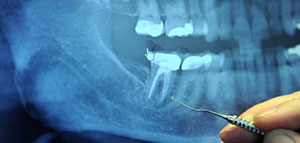

جاءت تسمية ضرس العقل بهذا الاسم كونه آخر الاسنان الطبيعية التي تجدها في الفم إضافة لظهوره غالبا بفترة نضج الإنسان العقلي وذلك ما بين عمر 18 إلى 25 عام كما وتجد أربعة منه اثنان في الفك السفلي واثنان في الفك العلوي وضرس العقل بدوره يبقى أكثر الأسنان المتعرضة لعدم بزوغها وانطمارها كما وقد تكون غير ظاهرة أبدا في بعض الأحيان

وذلك يرجع لكونها في أغلب الأحيان لا تجد لها مكانا يتسع لظهورها مما يؤدي كما ذكرنا مسبقا لعدم بزوغها أو انطمارها أو عدم ظهورها ونضيف إلى ذلك إمكانية ظهور جزء منها في الفم مع بقاء الجزء المتبقي منها مدفون في عظام الفك تحديدا

وفي بعض الحالات يفضل طبيب الأسنان خلع ضرس العقل من باب الوقاية نظرا لرؤيته بأن ضرس العقل في حالته هذه قد يؤدي لإصابة الشخص بالتهابات وآلام هو بغنى عنها وغالبا ما تتم عملية خلع ضرس العقل في المستشفى وينصح الشخص قبل خضوعه للعملية باتباع ارشادات ونصائح معينة كعدم شربه أو أكله لأي شيء في منتصف ليل اليوم الذي يسبق يوم العملية